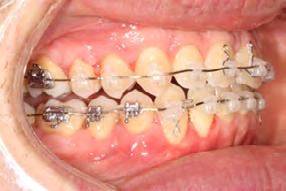

Approximately six months after insertion of the RPE, digital scans were taken for SureSmile custom wires and the patient was scheduled for the SFOT procedure with the oral surgeon. The RPE was removed, SureSmile wires inserted and segmental corticotomies performed, immediately followed by further vertical elastics on the right side (Figure

4). Archwires were upgraded incrementally into 19 x 25 SS. Once the bite was completely closed, the patient was referred to the myofunctional therapist to begin treatment. Eight sessions of myofunctional exercises were performed, focusing on muscle building, toning, synchronicity and awareness. Improvement in correct chewing, swallowing and resting postures of the lip and tongue were addressed. All appliances were removed 21 months after initial insertion (Figure 5), and the patient was referred to a re-

Figure 4. Post-corticotomy, with SureSmile custom wires.